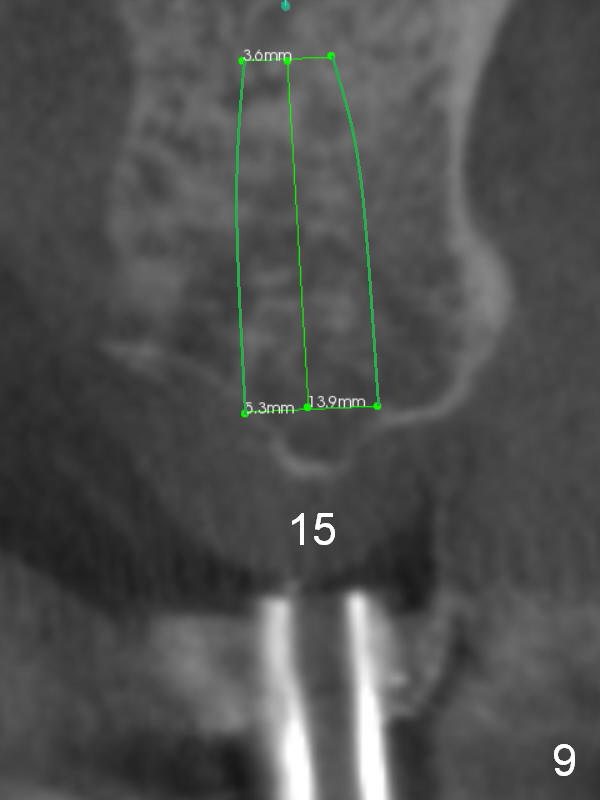

CBCT confirms that the ridge at #14 is narrower than that at #15. In contrast, the bone density is lower at #15 than that at #14 (Fig.7-9). If the keratinized tissue is wide, use 4 mm tissue punch (3 mm from #13). If incision is made, wheel saws will be used to split the ridge. Or use Magic split and osteotomes. Bone expanders are going to be used for bone expansion at #14 and bone condensation at #15 (Fig.8,9). Be careful while using bone expanders at #14, since the bone density is higher. There is a chance of plate fracture. Use drills if indicated. Fabricate splinted provisional after placement of abutments.